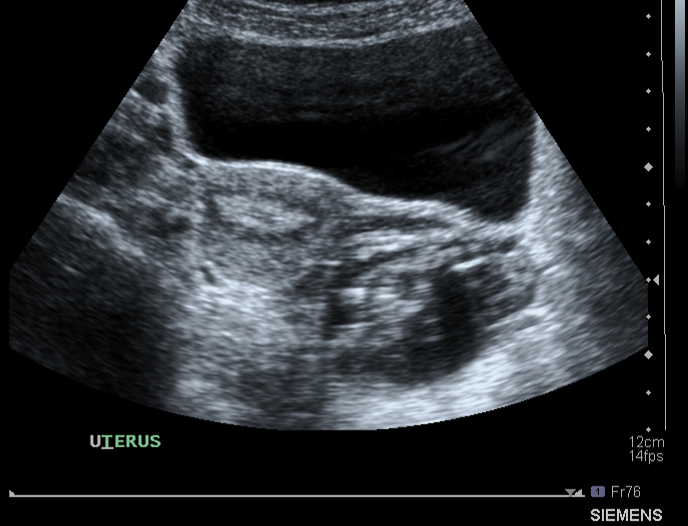

Go over the strctures seen in the sagittal transabdominal US

Key points to remember to help interpreting:

What structure is being shown in this US pic ?